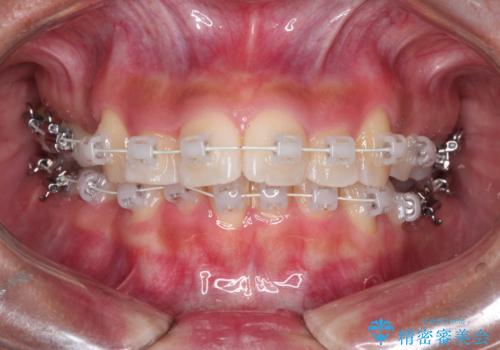

凸凹を綺麗にしたい。表側ワイヤー矯正

- 矯正装置

- 審美装置

- 前歯の凸凹を主訴に来院されました。

抜歯を行い、ワイヤー矯正にて治療を行いました。

凸凹もなくなり、歯磨きもしやすくなったと喜んでいただきました。